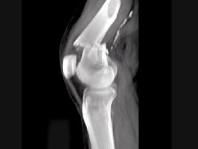

问题 男,45岁,车祸后左膝部剧痛,活动受限2小时,结合影像学检查,最可能的诊断是?(?)

选项 A.股骨颈骨折 B.股骨下端骨折 C.柯莱斯骨折 D.胫骨骨折 E.腓骨骨折

答案 B